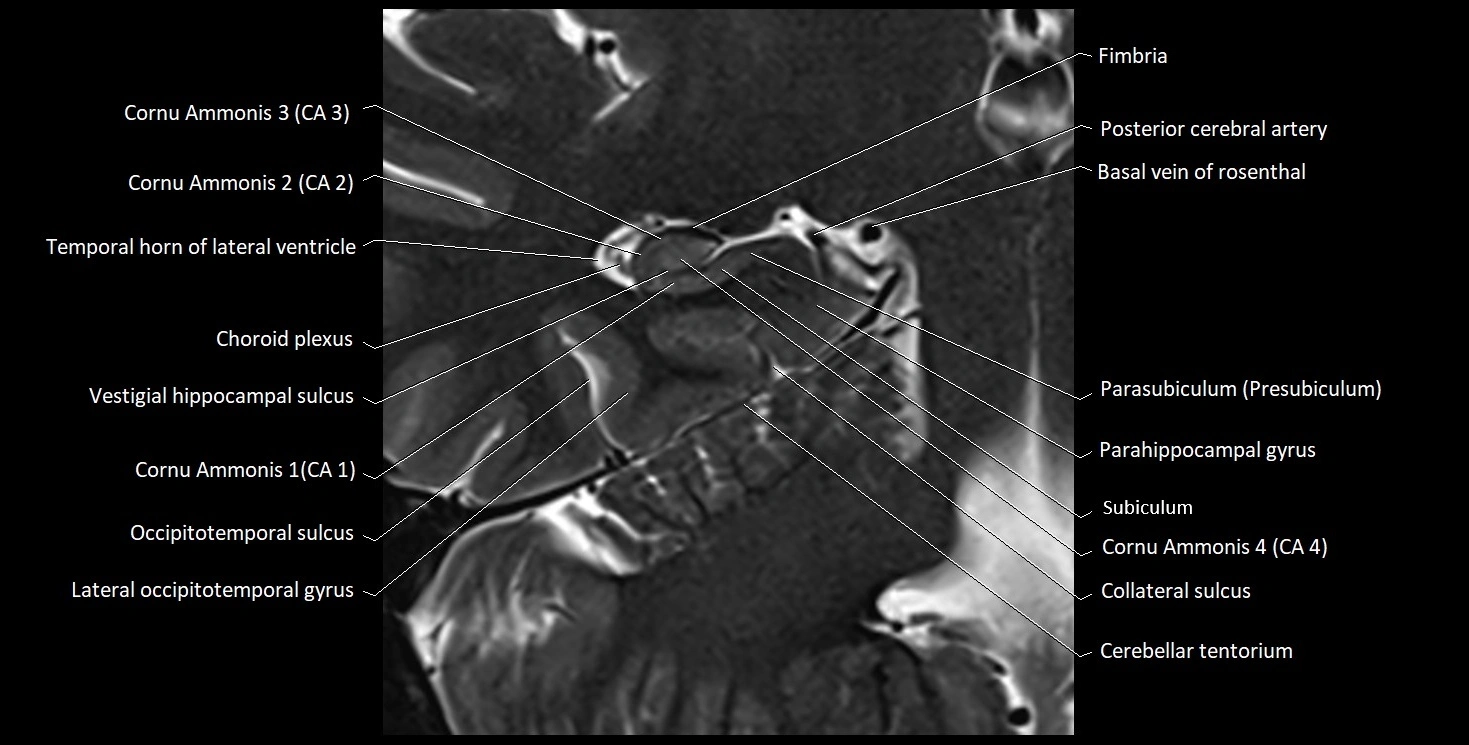

MRI images

image